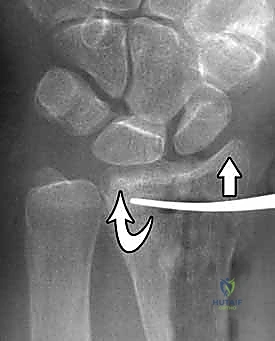

تُعرف كسور الكعبرة البعيدة بأنها تشمل منطقة الكردوس (Metaphysis)، وتحديداً المنطقة الواقعة ضمن طول السطح المفصلي الذي يعادل أوسع جزء من الرسغ بأكمله. في عياداتنا، نقوم بتقييم هذه الكسور بدقة متناهية بناءً على عدة خصائص رئيسية تحدد مسار العلاج:

- الموقع والاتجاه: هل يشمل الجانب الأمامي (الراحي - Volar) أم الخلفي (الظهري - Dorsal)؟

- امتداد الكسر: هل هو خارج المفصل (Extra-articular) أم داخل المفصل (Intra-articular)؟

- درجة التفتت: هل العظم مكسور إلى قطعتين أم مفتت إلى عدة شظايا؟

يعتمد الدكتور محمد هطيف على أحدث التقنيات التشخيصية، حيث يبدأ بـ الأشعة السينية (X-rays) في وضعيات متعددة. وفي حالات الكسور المعقدة التي تمتد إلى داخل المفصل، يتم إجراء تصوير مقطعي محوسب (CT Scan) لبناء صورة ثلاثية الأبعاد للكسر، مما يساعد في التخطيط الجراحي الدقيق.